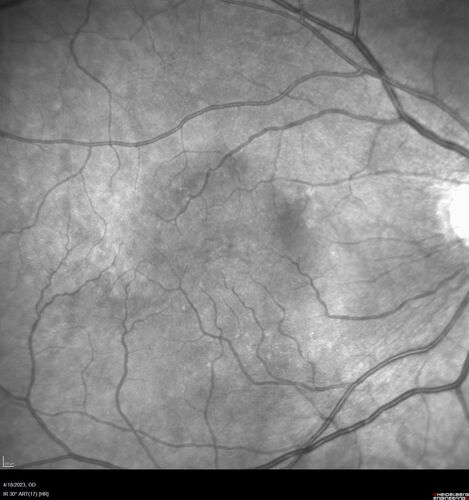

Lamellar Macular Hole and Good Vision

67 year old woman with good vision and floaters - VA 20/32 OD, 20/23 OS

LamellarMH_114951_041823_05.jpg

Lamellar Macular Hole Good Vision